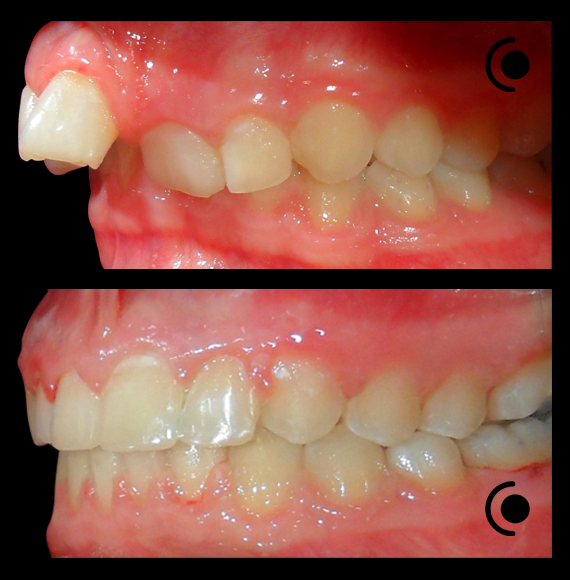

O našoj kvaliteti najbolje govore naši rezultati!

Centar za ortodonciju Petra Džapo